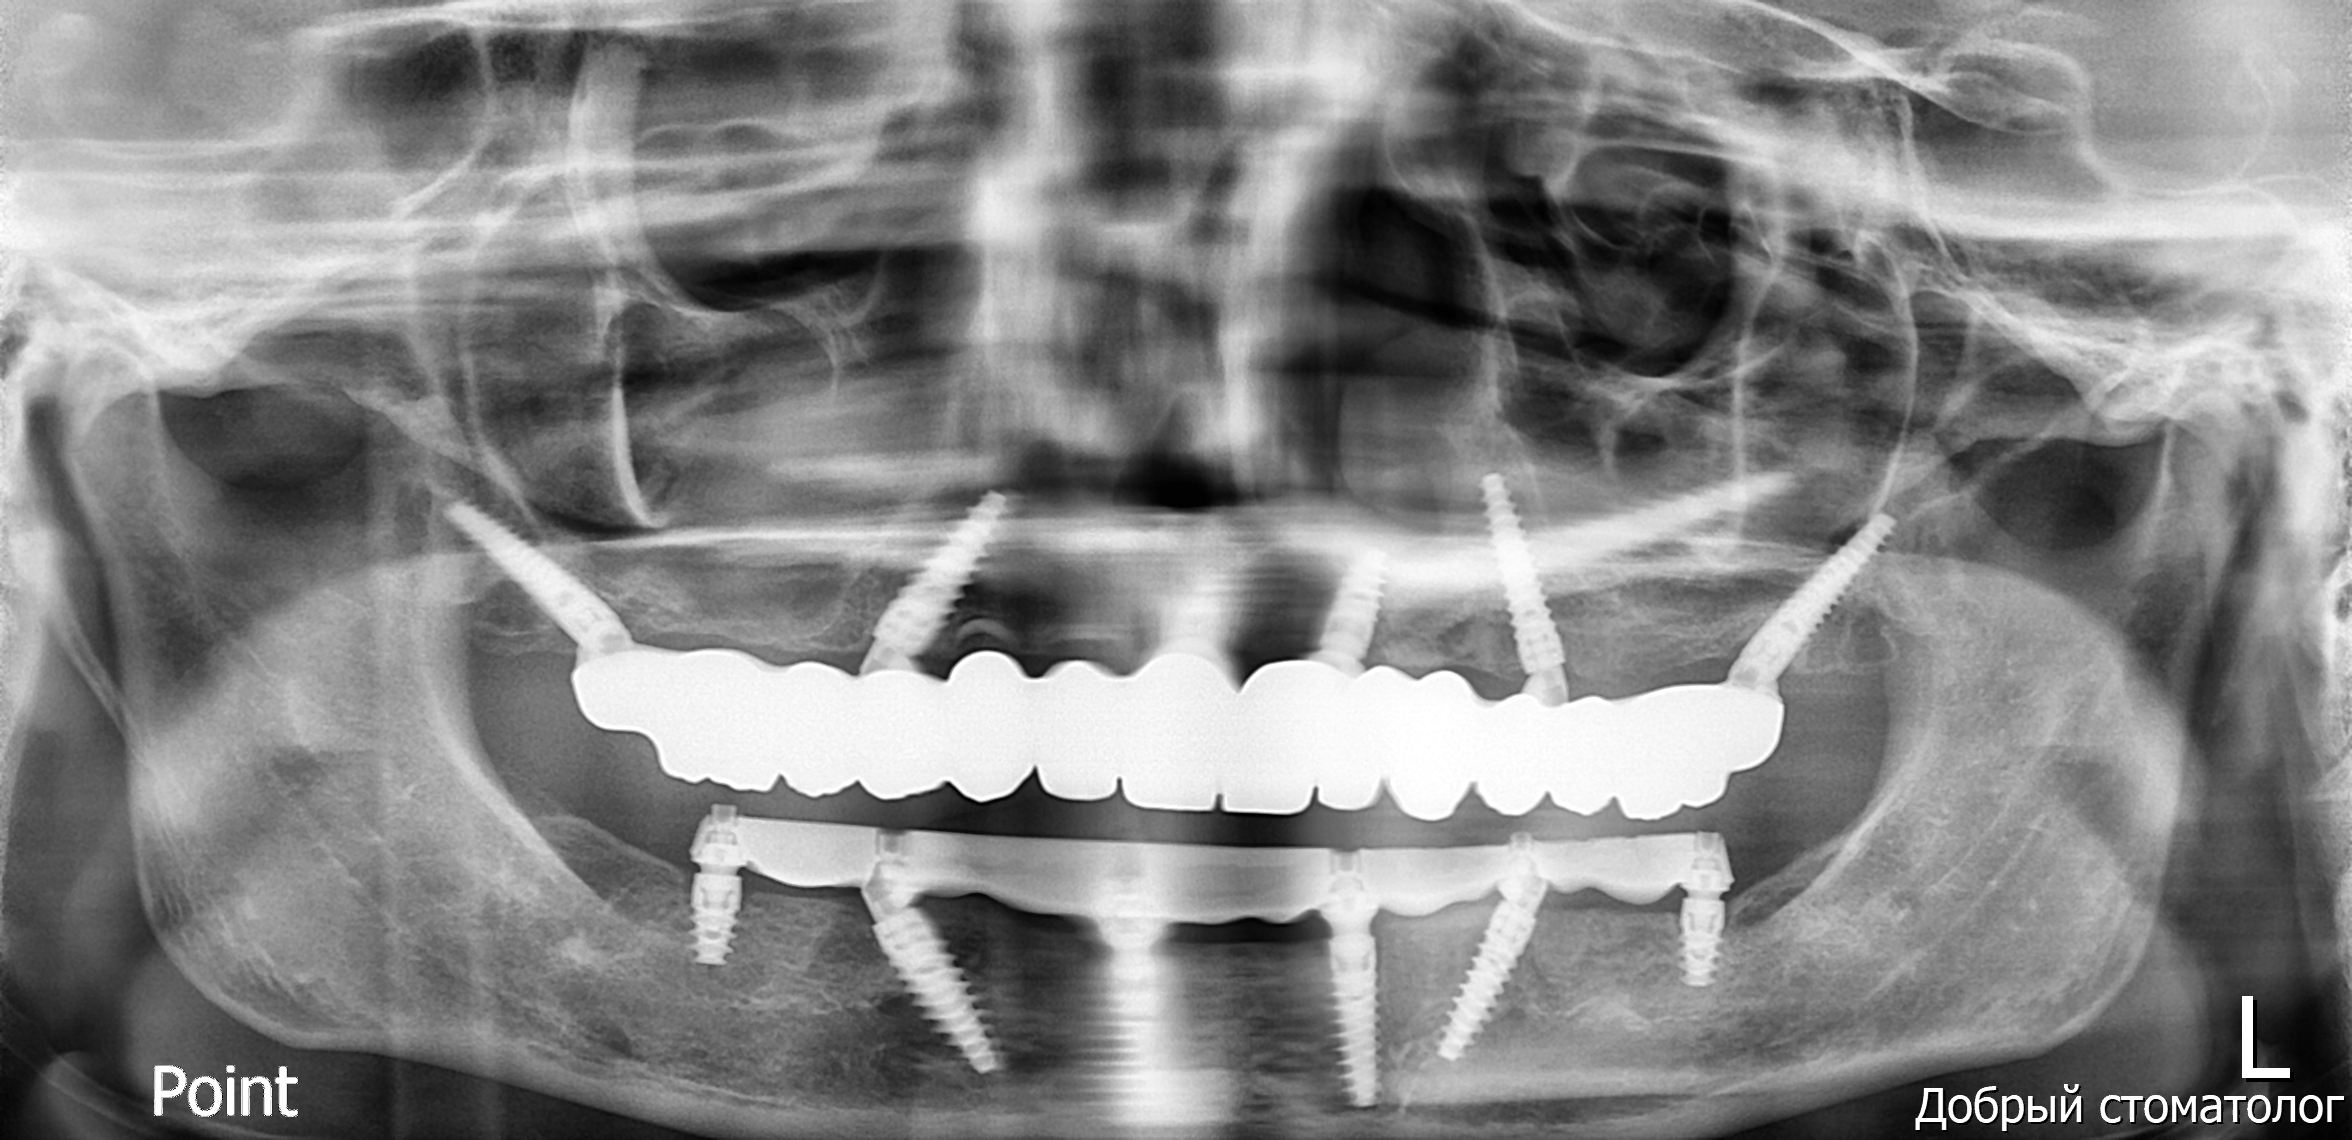

Based on the high-fidelity digital impressions, same-day resin provisional prostheses were fabricated and delivered immediately after surgery. The precision of the IPG scan ensured a successful same-day provisional bridge delivery and secure retention using Rosen screws without the need for titanium bases. Post-operative Orthopantomogram (OPTG) confirmed accurate seating and stable connections across all implants, with a 2 mm occlusal clearance maintained in the molar region to ensure functional safety during the initial healing phase.

At the six-month follow-up, the patient reported high satisfaction with the functional and aesthetic performance of the provisional restorations. Clinical examination following the removal of the provisionals revealed optimal soft tissue healing and well-preserved gingival architecture. Notably, the Root Shield sites at 13, 12, and 23 successfully maintained the buccal ridge contour, while radiographic evaluation (OPTG) confirmed complete osseointegration of all implants, including the pterygoid fixtures at sites 17 and 27.